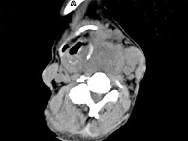

问题 女,64岁,发现双甲状腺肿大一月余,CT如图所示,最可能诊断为 ( )

选项 A、甲状腺转移癌 B、甲状腺结核 C、甲状腺腺瘤 D、甲状腺癌并淋巴结转移 E、结节性甲状腺肿

答案 D